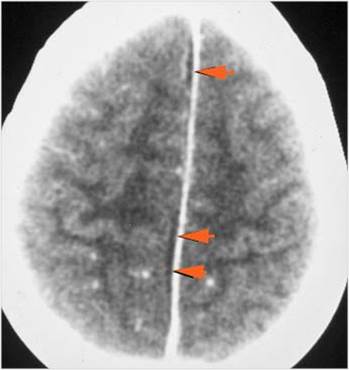

There is evidence of thrombus, thrombophlebitis or other occlusive or inflammatory process of the cortical veins, sphenoparietal sinus or sagittal sinus. [Yes/No]